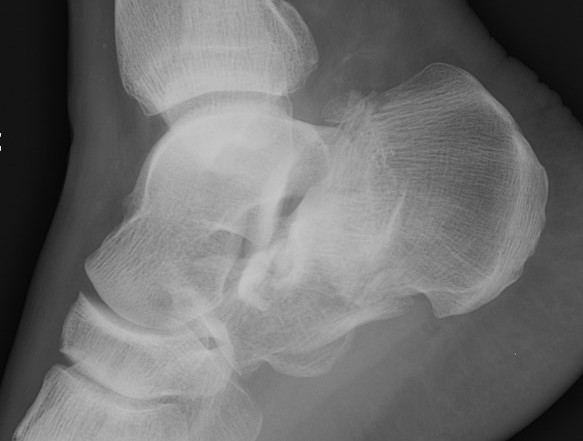

- 287 displaced intra-articular fractures

- MUA / Gissane spike percutanous reduction / K wire fixation

- 72% good or excellent results

- 1.7% deep infection, 7% superficial infection